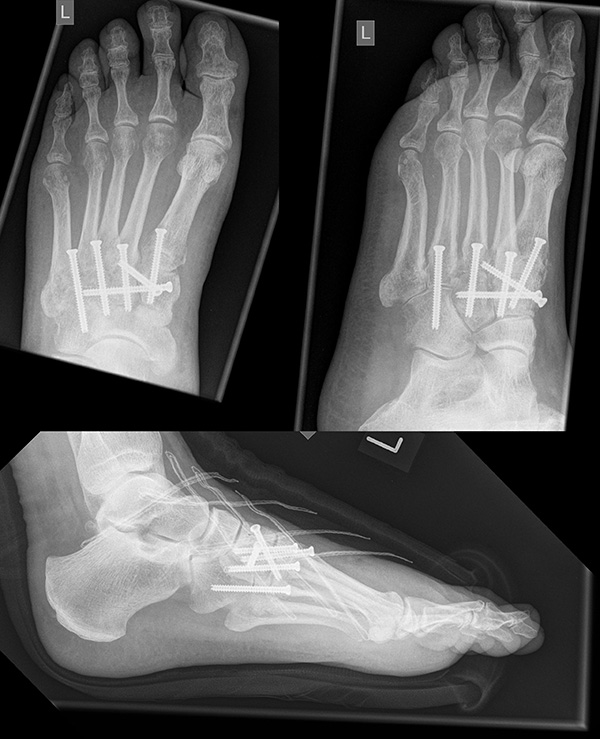

In der Regel werden die physiologisch rigiden TMT-1 bis 3 mittels Schrauben transfixiert. Hierfür werden meist kanülierte Kleinfragment-Kortikalisschrauben (3,5 oder 4 mm) verwendet. Diese können in Stellschraubentechnik von der Metatarsale-1-Basis in das Os cuneiforme mediale (Abb. 17) sowie vom Os cuneifome mediale in die Metatarsale-2-Basis und bei zusätzlicher intercuneiformer Instabilität vom Os cuneifome mediale in das Os cuneifome intermedium eingebracht werden.

Zum Lesen der Bildbeschreibung und zur Vollansicht bitte das Bild anklicken.

Ggf. wird zusätzlich ein K-Draht oder eine Schraube von der Metatarsale-2-Basis in das Os cuneiforme intermedium gebohrt (Abb. 18). Zur Transfixation der TMT-4 und 5-Gelenke werden, entsprechend ihres höheren physiologischen Bewegungsumfangs meist K-Drähte empfohlen. Die Indikation zur Transfixation wird von den meisten Autoren nur bei einer Instabilität gesehen, einige empfehlen eine Transfixation sämtlicher TMT-Gelenke unabhängig vom Ausmaß der Instabilität 10. Kleine, nicht refixierbare Fragmente sollten entfernt werden. Ist ein primärer Hautverschluss nicht möglich, erfolgt die temporäre Weichteildeckung mit Kunsthaut wie Epigard 112951710.

Wird die Entscheidung zur Arthrodese gefällt, sollten nur Gelenke mit einer symptomatischen Arthrose versteift werden. Meist genügt die Arthrodese der TMT-1 bis 3-Gelenke. Die Arthrodese kann mit Schrauben oder dorsalen Platten durchgeführt werden. Die betroffenen Gelenkflächen werden entknorpelt und das Gelenk mit einer Zugschraubentechnik oder einer dorsalen Platte stabilisiert (Abb. 19-22) 25 (Richter 2002; Richter 2007). Einige Autoren befürworten eine primäre Arthrodese auch bei rein ligamentären Verletzungen mit multidirektionaler Instabilität, da diese eine schlechte Heilungstendenz aufweisen und häufiger zu Korrekturverlust neigen 3617112.

Zum Lesen der Bildbeschreibung und zur Vollansicht bitte die Bilder anklicken.